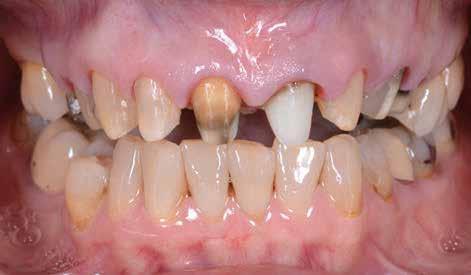

A 26 éves férfi páciens azzal a kéréssel kereste fel a rendelőnket, hogy a frontfogai esztétikusabb megjelenését szeretné elérni. A páciens jó általános egészségi állapottal rendelkezett, nem szenvedett allergiáktól és nem kellett rendszeresen gyógyszereket szednie. A páciens lehetőség szerint kerülte a fogai megmutatását. Rendkívül zavarónak találta a nagymetszői között, a középvonalnak megfelelően látható rést, a fogain látható kopási jeleket, valamint a fogai méretét is túl kicsinek találta. A szájüregi vizsgálat során megállapítottuk, hogy a nagymetsző fogai (11, 21) élharapásban vannak, valamint az alsó fogíven kismértékű torlódást észleltünk. A felső frontfogakon

(13-23) attrícióra utaló jeleket találtunk. A fogak kopása a nagymetszőfogaknak megfelelően volt a legkifejezettebb (1. ábra) . Az előbbiekben említett fogak (11, 21) ezen kívül némileg elfordultak, és jelentősebb méretű diasztéma volt köztük. A páciens Angle I.-osztályú állcsontrelációs helyzettel rendelkezett. A vizsgálat során feltűnt, hogy a páciens csak nagyon óvatosan mert mosolyogni (2. ábra)

A szájüregi vizsgálat során nem találtunk szuvas léziók jelenlétére utaló eltéréseket. A nagymetszőfogakon megfigyelhető jelentős mértékű kopás ellenére nem észleltünk craniomandibuláris diszfunkció jelenlétére utaló jeleket. A vizsgálat befejezését követően a pácienst tájékoztattuk a különböző kezelési lehetőségekről. Az esztétikai megjelenés javítása érdekében először egy alignerekkel végzett fogszabályzó kezelés elvégzését, majd a harapási helyzet optimalizálását követően a felső frontfogai kompozittal történő direkt felépítését vagy héjakkal történő ellátását (pl.: non-prep héjak) javasoltuk (3. és 4. ábra).